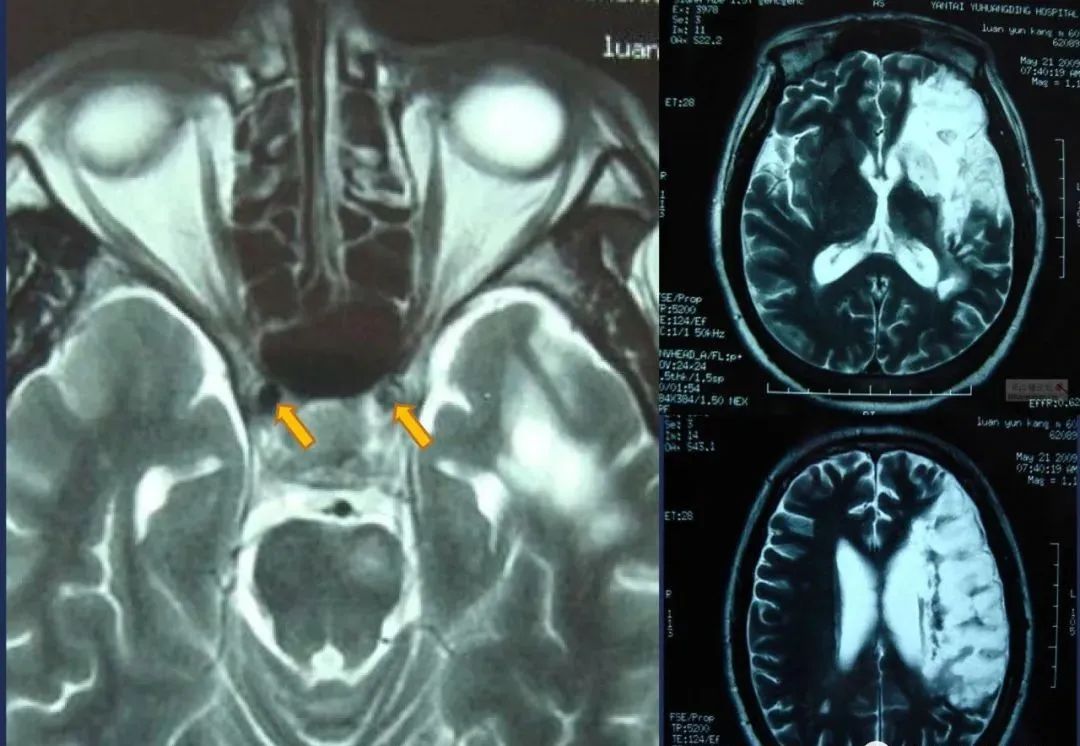

椎基底动脉梗死大脑后动脉丘脑穿通动脉-Percheron动脉